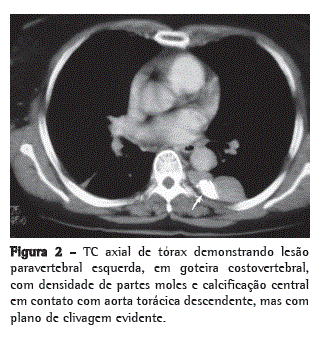

A radiografia de tórax evidenciou uma massa em topografia de mediastino posterior, que foi confirmada no pré-operatório por TC de tórax, na qual foi identificada uma massa heterogênea com calcificação densa em topografia de goteira costovertebral esquerda (Figuras 1 e 2).